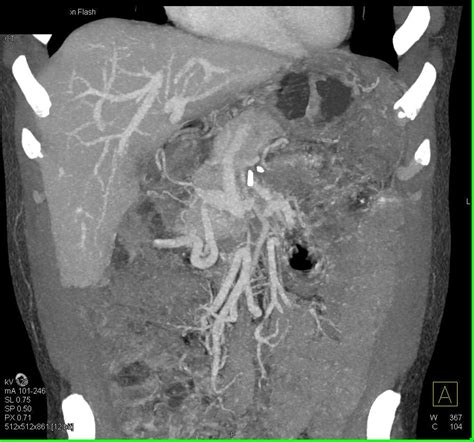

Let’s really emphasize why the pancreas is a vital organ we can’t ignore . It’s easy to overlook because it’s tucked away, but trust me, it’s a powerhouse. Imagine your pancreas as the ultimate multitasker of your digestive system and endocrine system. On the digestive front, it churns out a cocktail of powerful enzymes – think amylase for carbs, lipase for fats, and proteases for proteins. Without these, your body would struggle to break down your food effectively, meaning you wouldn’t absorb the nutrients you need to fuel your body and keep everything running smoothly. This is digestion 101, and the pancreas is the star player. But its role doesn’t stop there, guys. The endocrine side of the pancreas is equally, if not more, critical, especially when we talk about blood sugar. It contains specialized cells, the aforementioned islets of Langerhans, which are like tiny hormone factories. The beta cells within these islets produce insulin, the hormone that tells your cells to take up glucose from your bloodstream for energy. The alpha cells produce glucagon, which does the opposite – it signals your liver to release stored glucose when your blood sugar drops too low. This intricate dance between insulin and glucagon keeps your blood glucose levels stable, preventing the highs and lows that can cause all sorts of health problems, from immediate fatigue and mood swings to long-term damage to your nerves, eyes, and kidneys. Conditions like diabetes are directly linked to problems with insulin production or function, highlighting the pancreas’s central role. Therefore, any factor that impacts the pancreas, like OSCGPLPSC, has the potential to throw these delicate systems completely out of whack. It’s not just about feeling a bit off; it’s about maintaining the fundamental biochemical balance that keeps us alive and thriving. So, yeah, the pancreas? Super important , and we absolutely cannot afford to ignore it.